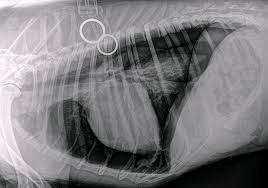

เปิด 5 สถิติน่ารู้ “ภาวะลมรั่วในปอดหมา (Pneumothorax)” อย่ารอให้น้องหอบถึงขั้นวิ่งไม่ไหว (อัปเดท 2025)

เปิด 5 สถิติน่ารู้เกี่ยวกับ Pneumothorax หรือภาวะลมรั่วในช่องเยื่อหุ้มปอดของสุนัข พร้อมอาการ วิธีวินิจฉัย การรักษา และการป้องกันสำหรับเจ้าของหมาทุกคน